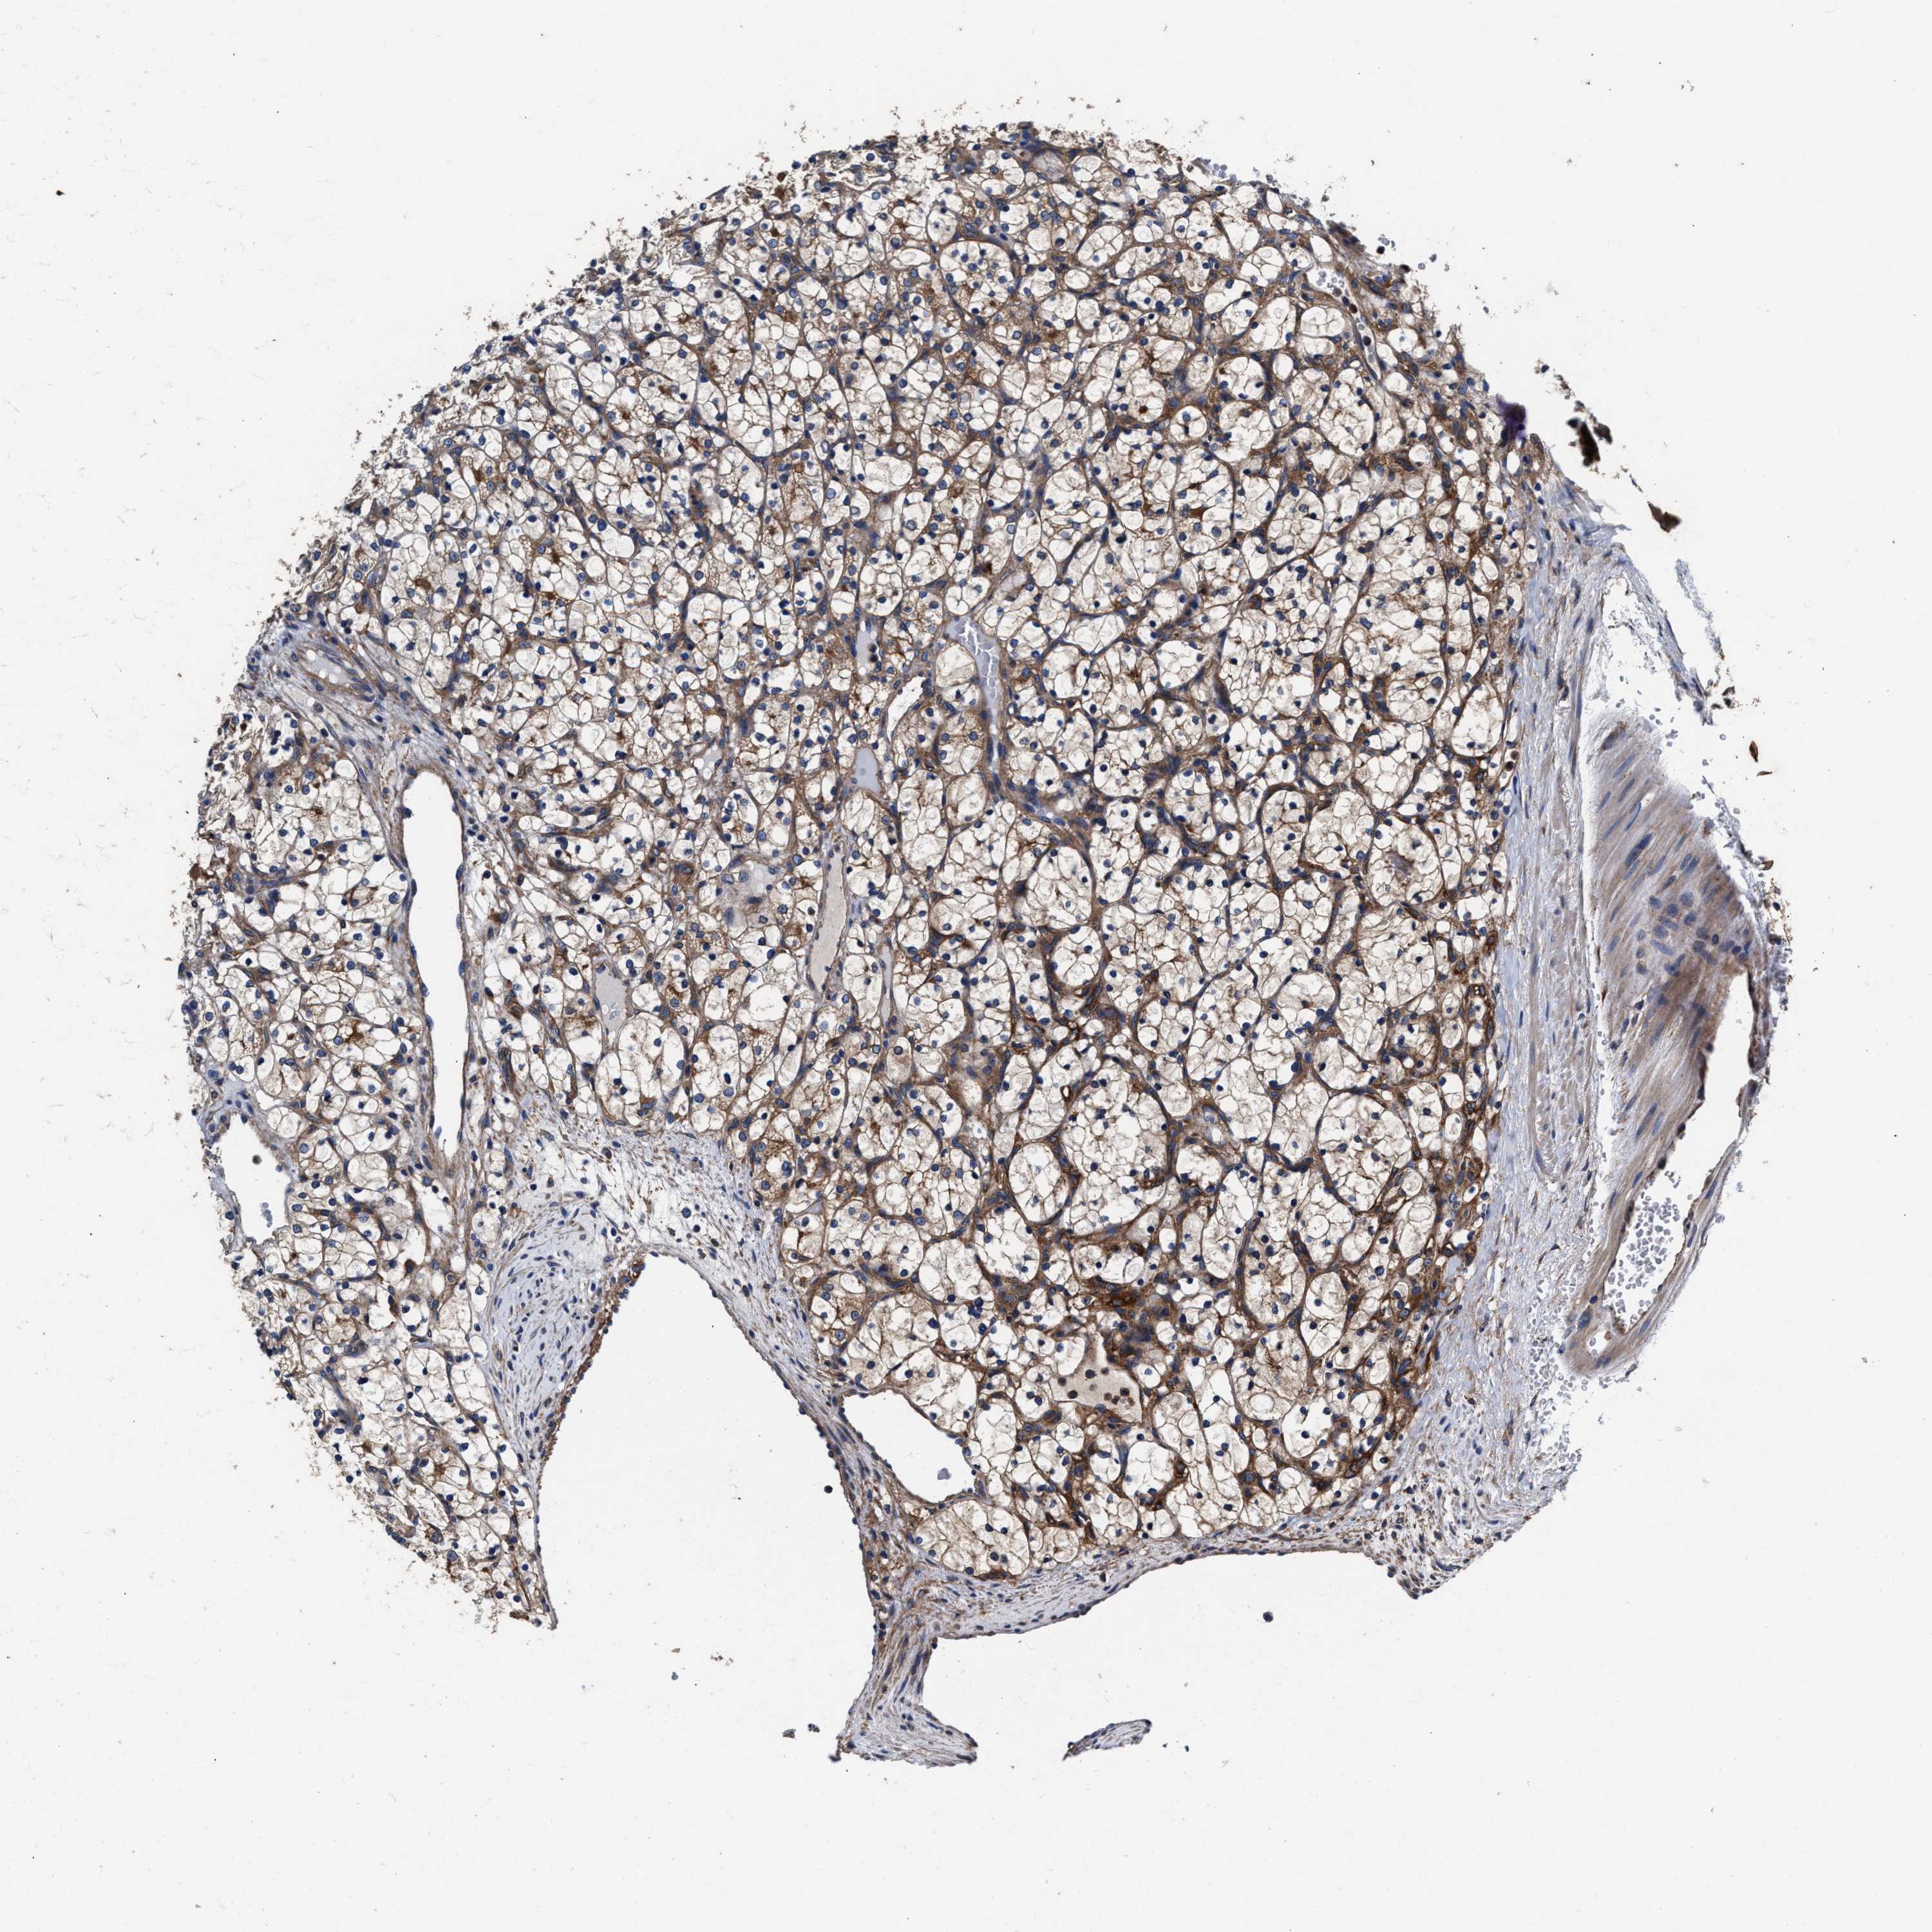

CANCER RENAL CANCER Show tissue menu

KICH TCGA KIRC TCGA KIRC VALIDATION KIRP TCGA PROTEIN RCC CPTAC PROTEIN EXPRESSION